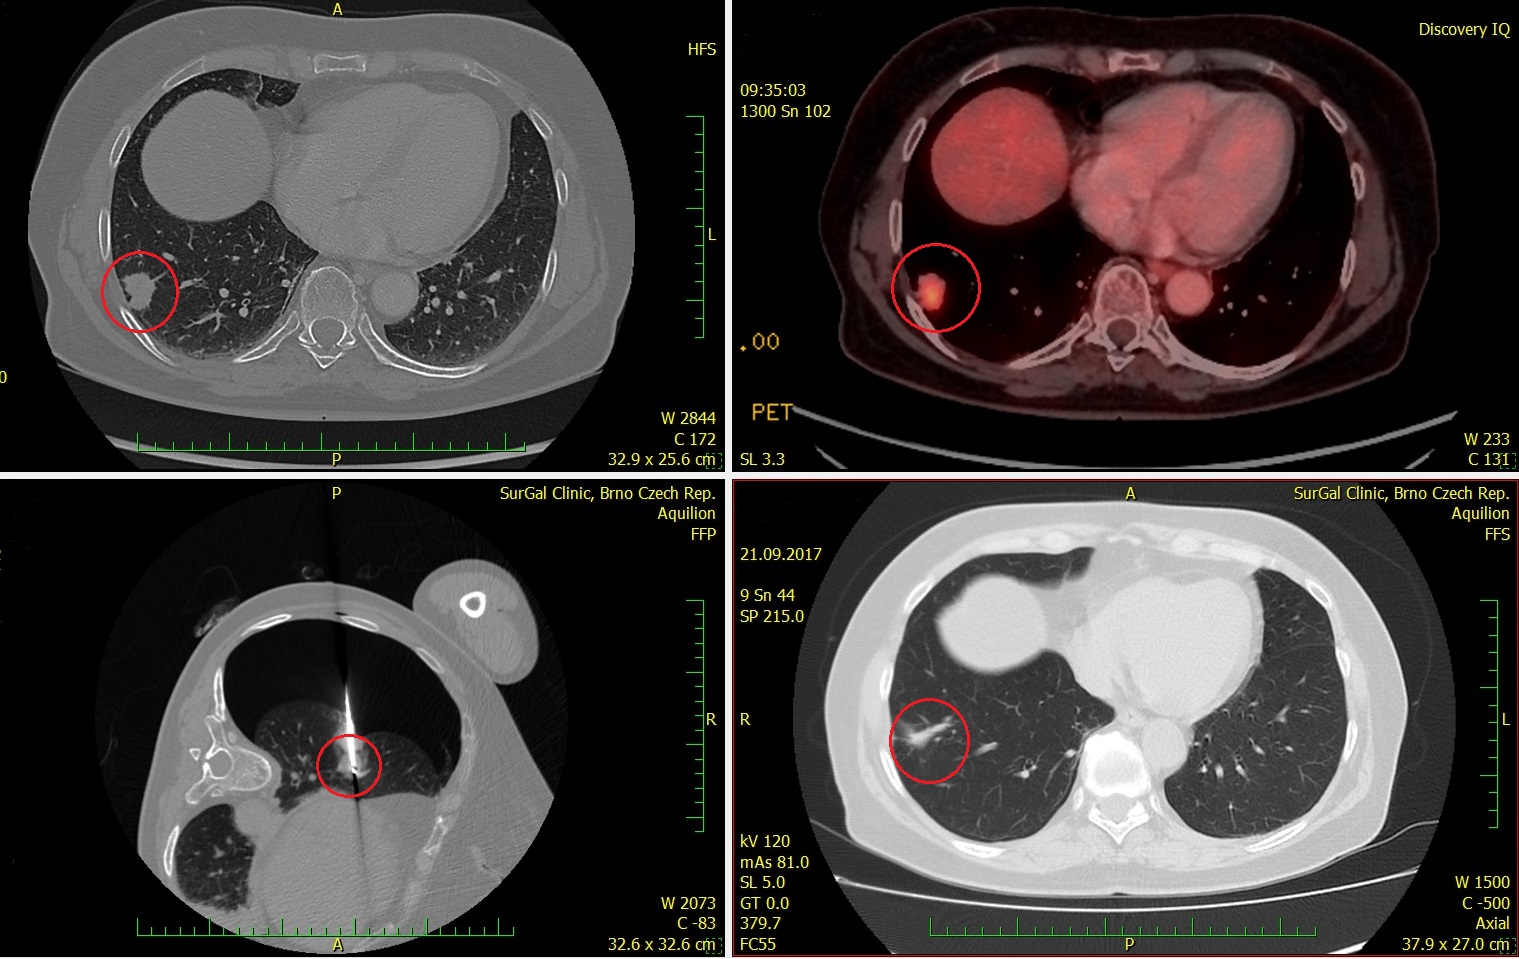

Zákrok byl proveden v červenci 2017, proběhl bez podstatných komplikací, na kontrolním vyšetření v září 2017 je patrné kompletní vymizení ošetřených ložisek primárního nádoru i metastázy (viz CT nález) a pacient je schopen normálního života. Péči hradí zdravotní pojišťovna.

- 21.9.2017 kontrolní CT, SurGal Clinic, další CT plánováno na 12/2017